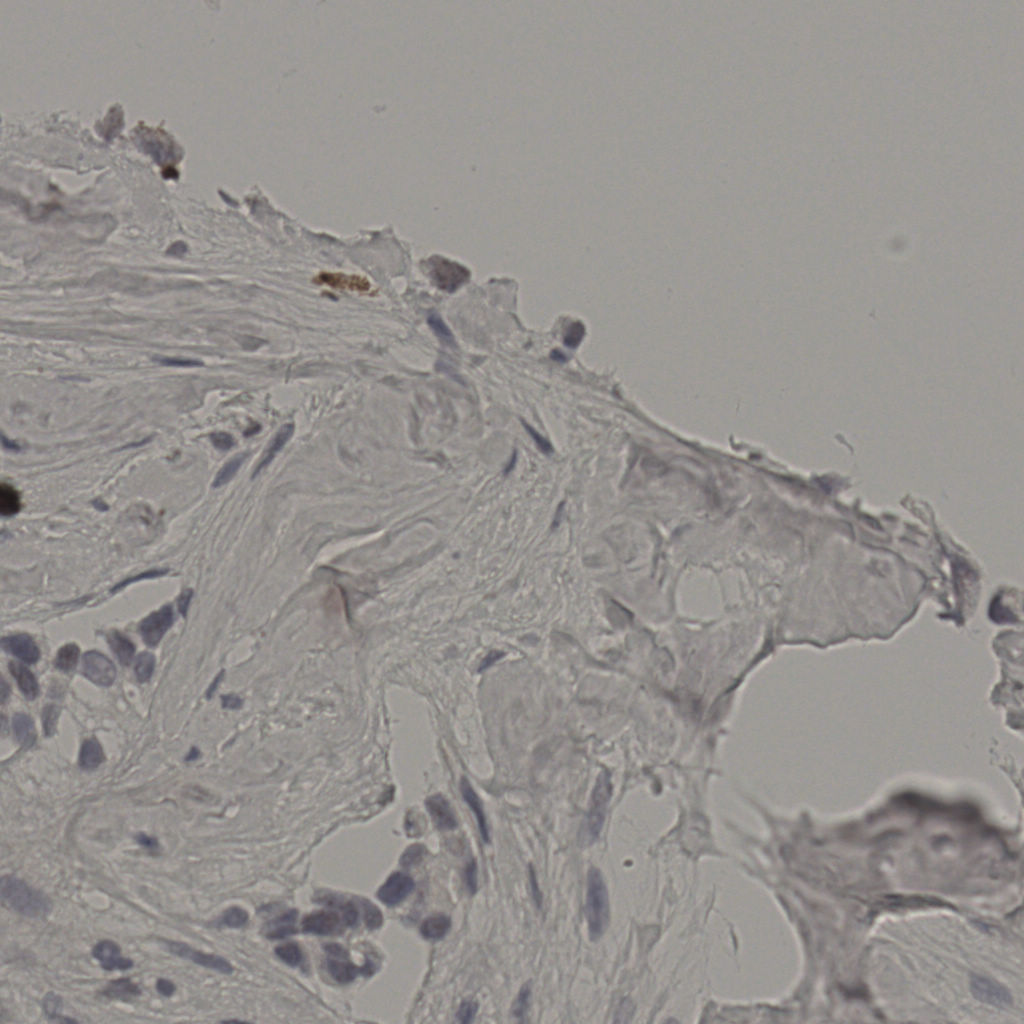

标记后

标记前